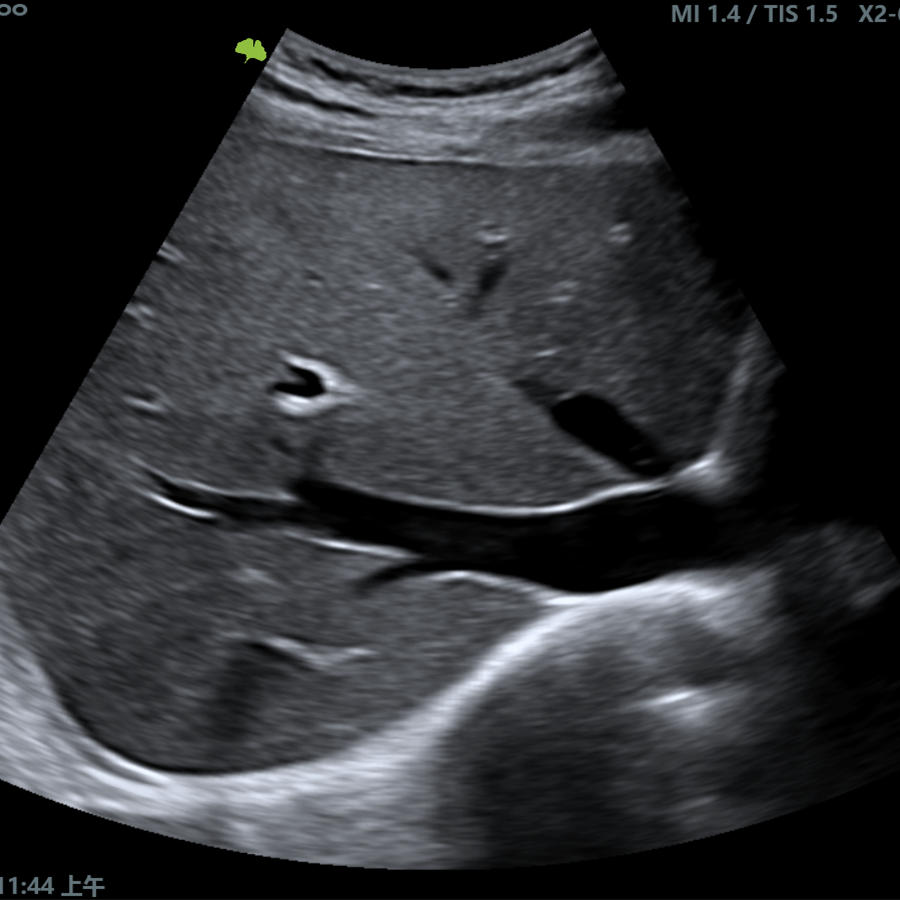

El VINNO R300 redefine la claridad de las imágenes por ultrasonido y la ergonomía siendo ahora mucho más fácil de usar, mejorando la experiencia del escaneo. Está diseñado para cumplir con las expectativas como un sistema de servicios compartidos altamente eficiente. Destacan su rendimiento e imagen excepcionales, aplicaciones extensas, workflow eficiente y diseño amigable y cómodo.

Doppler

- Modo B

- Modo M

- Modo CFM (Color)

- Modo DPI (Power)

- Modo PW (Pulsado)